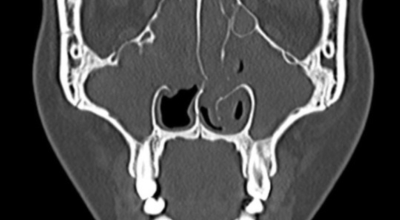

얼굴의 뼛속에는 몇 개의 빈 공간이 있습니다. 이러한 빈 공간을 '코 옆에 있는 동굴들'이라고 부르는 의미에서 부비동이라 해요. 이 공간은 머리 뼛속에 있는 뇌를 외부의 쇼크으로부터 보호해 주는 역할을 해요. 부비동염은 이러한 부비동이라는 빈 공간에 세균, 바이러스가 침투해서 염증이 발생한 질환을 의미해요. 부비동염은 흔히 '축농증'이라고 불립니다.

부비동염은 증상과 기간에 따라 '급성 부비동염'과 '만성 부비동염'으로 구분되어요. 부비동 코 주위의 얼굴 뼛속에 있는 빈 공간은 숨 쉬는 공기의 온도와 습도를 조절하며, 외부의 쇼크으로부터 뇌를 보호해요. 부비동은 작은 구멍을 통해 콧속과 연결됩니다. 이를 통해 콧속이 환기되고 부비동 내의 분비물이 자연스럽게 콧속으로 배출되어요. 부비동염은 이 부비동에 염증이 발생해서 콧물이 배출되지 못하고 고여 있는 상태를 말해요.